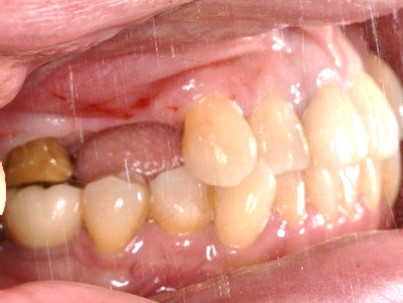

Before

【抜歯後】